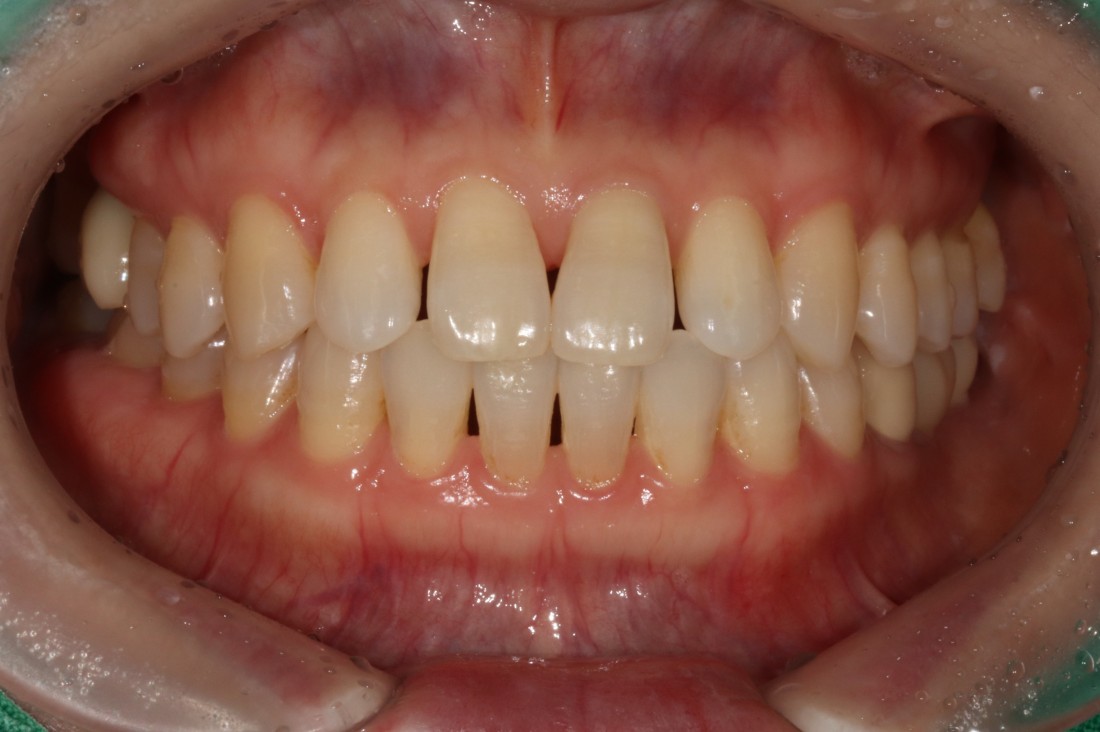

광주 무삭제 라미네이트 치과를 검색하면

정말 많은 치과가 나오는데요.

광고성 글이 아닌

진짜 라미네이트 진료 전/후 사진을

투명하게 공개하는 치과가

가장 신뢰할 수 있으실 겁니다.